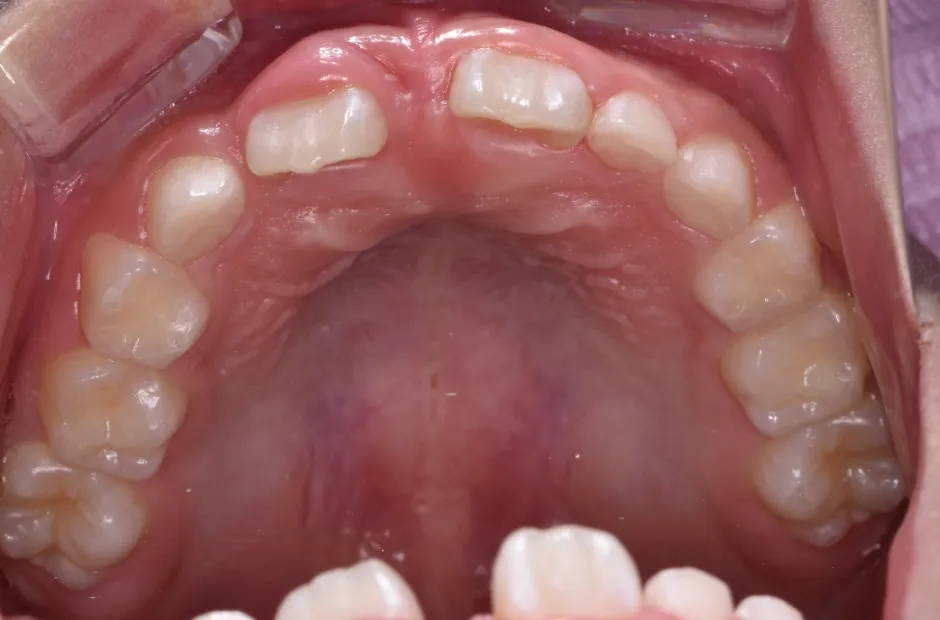

前歯部反対咬合とすきっ歯

| 診断名・主訴 | 前歯部反対咬合とすきっ歯 |

|---|---|

| 年齢・性別 | 7歳・女性 |

| 治療期間・回数 | 1年半、月一回 |

| 治療に用いた主な装置 | 床拡大装置+ブラケット(前歯部) |

| 抜歯部位 | なし |

| 治療費 | 30万円(税抜) |

| リスク・副作用 | 装置による違和感・疼痛・歯肉退縮・歯根吸収・虫歯のリスクなど |

治療前

治療後